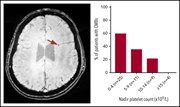

Identification of occult cerebral microbleeds in adults with immune thrombocytopenia

Management of patients with immune thrombocytopenia (ITP) seeks to minimize morbidity both from severe bleeding and from therapy, with cerebral hemorrhage being a feared event. Cooper and colleagues used highly sensitive susceptibility-weighted magnetic resonance imaging to detect asymptomatic cerebral microbleeds (CMBs) in over 50% of patients with ITP and a platelet count of <5 × 109/L, with a lower frequency at higher counts. These data will prompt further evaluation of this imaging technique in ITP, particularly as mucosal and skin bleeding scores may not predict CMBs.